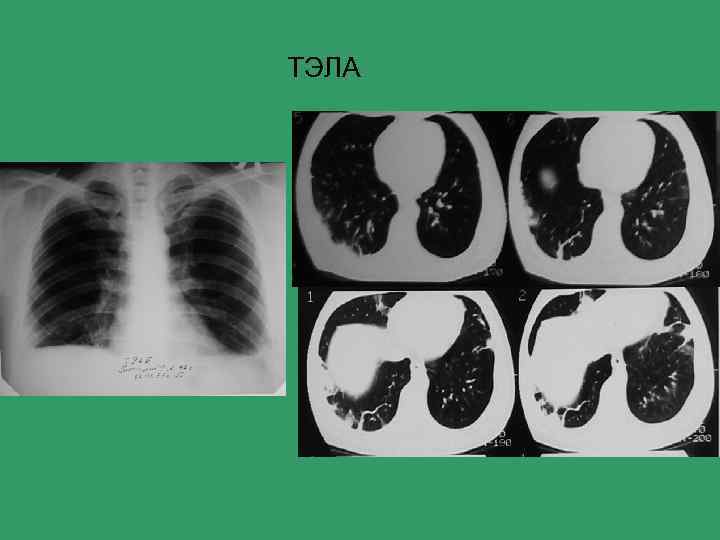

ТЭЛА